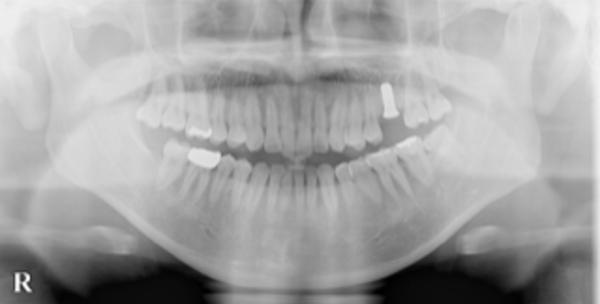

抜歯4ヶ月後に、治療部分のCTの撮影を行い、骨の形、量、幅などインプラント治療が可能かどうかを評価しました。

抜歯部には十分な骨の量があり、インプラント治療が可能であると判断しました。

治療後エックス線写真にて埋めたインプラントの確認を行い、問題ないことを確かめ処置終了としました。なお、治療時間は1時間弱でした。